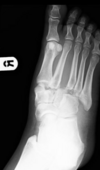

Fx de Jones Base del 5to metacarpiano